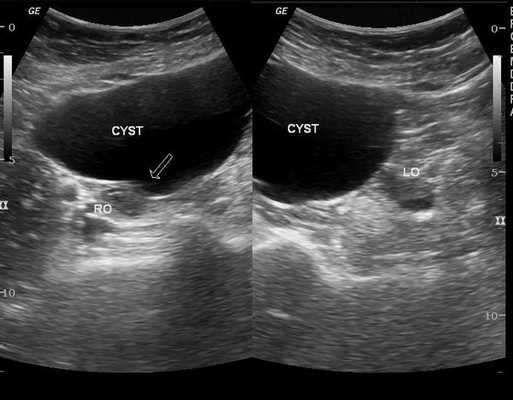

В процессе трансвагинального УЗИ определяется округлое или овоидное тонкостенное образование с однородным анэхогенным содержимым, реже - с мелкодисперсной взвесью внутри. Эхоскопическим критерием параовариальной кисты служит визуализация интактного яичника. Параовариальную кисту дифференцируют с внематочной беременностью, кистой яичника, истинными опухолями яичника.

При ультразвуковом исследовании влагалищным или абдоминальным датчиком определяется округлое тонкостенное образование с однородным содержимым, которое выглядит тёмным пятном. Иногда внутри определяется мелкодисперсная взвесь.

Важным критерием, указывающим на параовариальную кисту, является незатронутый яичник, который видно при УЗИ.

Перегородки в кисте, сосочкообразные выросты и пристеночные включения — неблагоприятные признаки, которые могут указывать на неоплазию (онкопатологию).